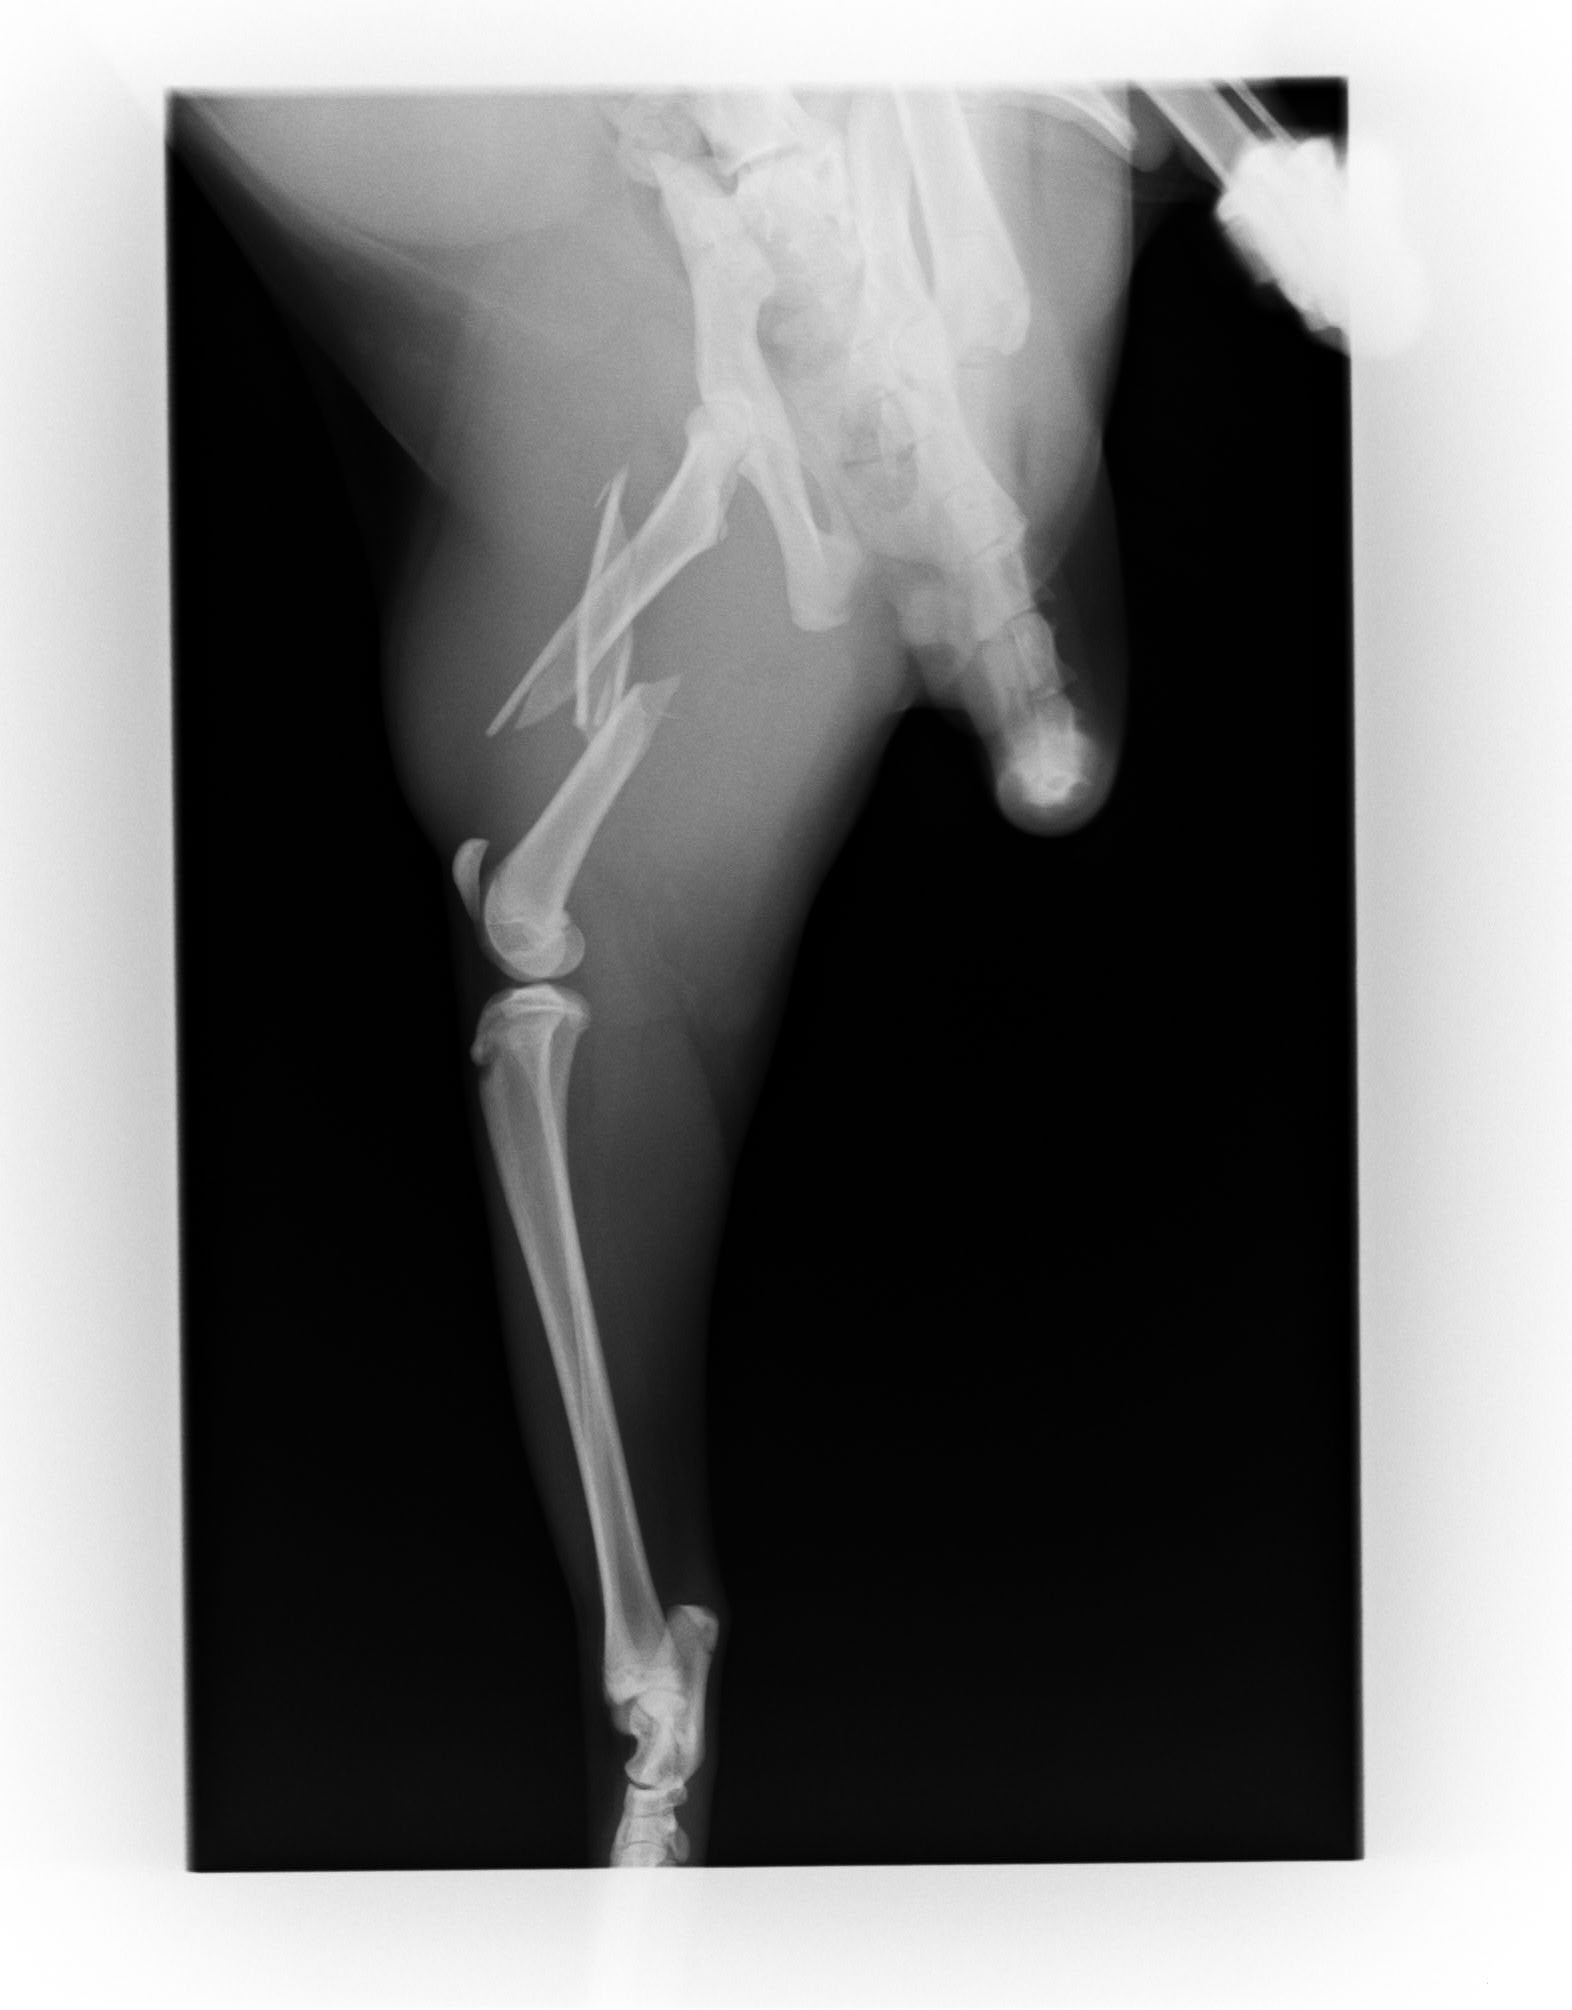

さて今回のブログは先日当院で行った猫ちゃんの骨折について載せさせていただこうと思います。

大腿骨の粉砕骨折のため入院し手術を行いました。